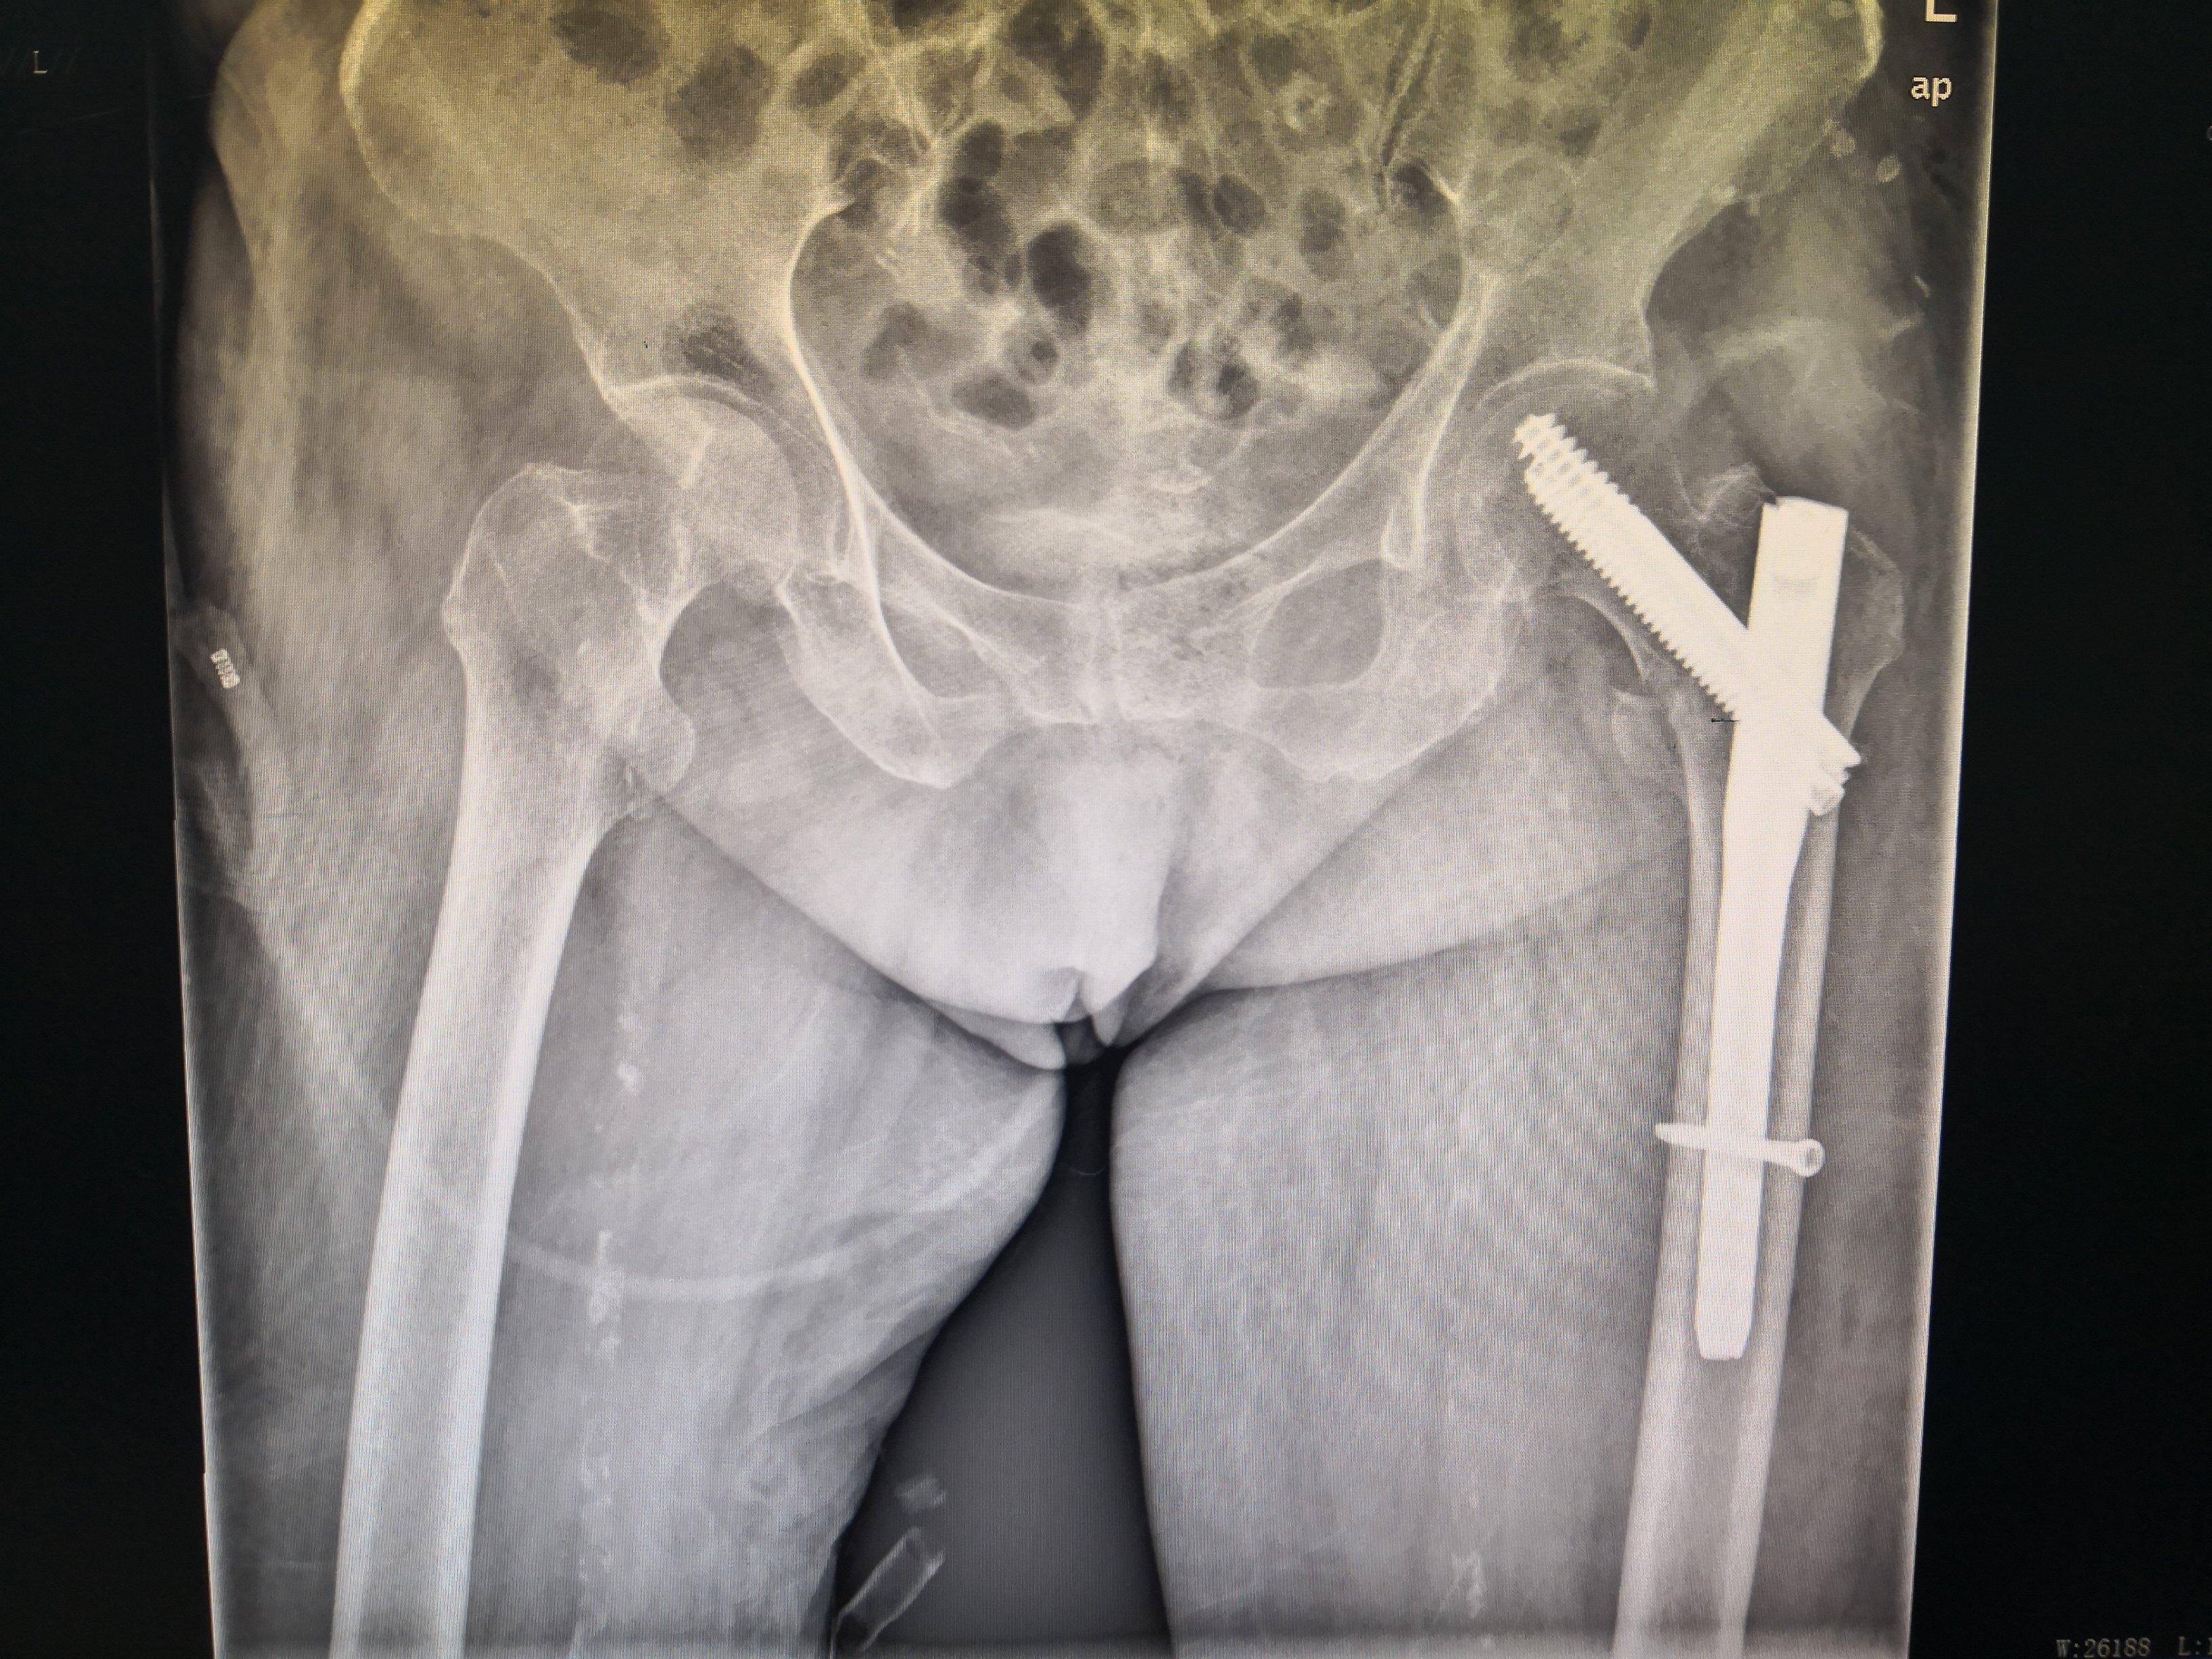

图片经患者同意才上传。下面我把几个患者的术前骨折片及术中、术后X光片传上来让大家有个认识。

很幸运,5例手术效果都很好。总结一下:股骨转子间骨折是老年髋部骨折最常见的类型,特别是骨质疏松的老年女性,下雨天不要让老人出门,厨房、洗水间要装防滑的软垫,老人房间没洗水间的,要准备尿不湿,很多老人夜尿多,半夜起床上洗水间不敢开灯,怕影响到别人。髋部受伤后要及时就医,拍X光片,确定股骨转子间骨折后不要认为合并有很多慢性病就拒绝手术,能不能手术由医生做完检查后评估,这类手术是能微创做的,使用lNTERTAN髓内钉技术,能让骨折恢复力线,没有疼痛,早期能坐轮椅外出和下床行走,提高生命质量,享受更快乐的晚年。感谢5位并肩作战和支持我的老人家,你们的笑容很灿烂,我会永远记得的!